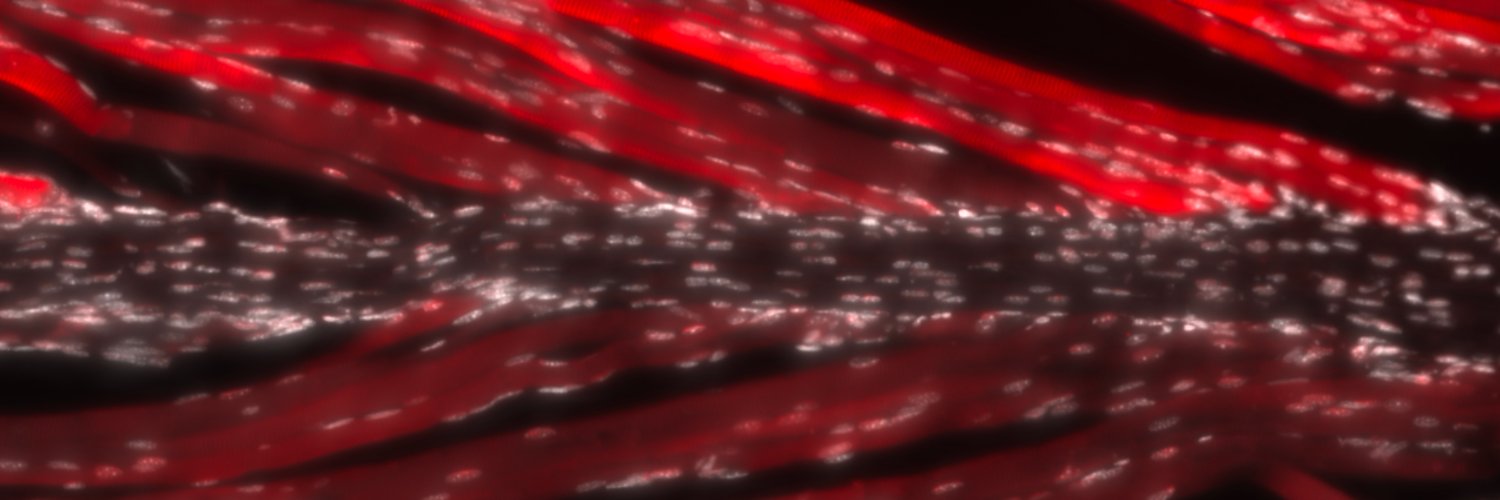

New Insights into Neuromuscular Contracture Reveals Myotendinous- SMAD4 Signaling Underlies Contracture Formation biorxiv.org/cgi/content/sh… #biorxiv_molbio